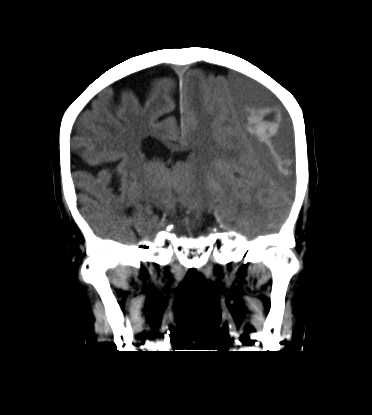

CT検査

内科領域

頭部

硬膜下血腫